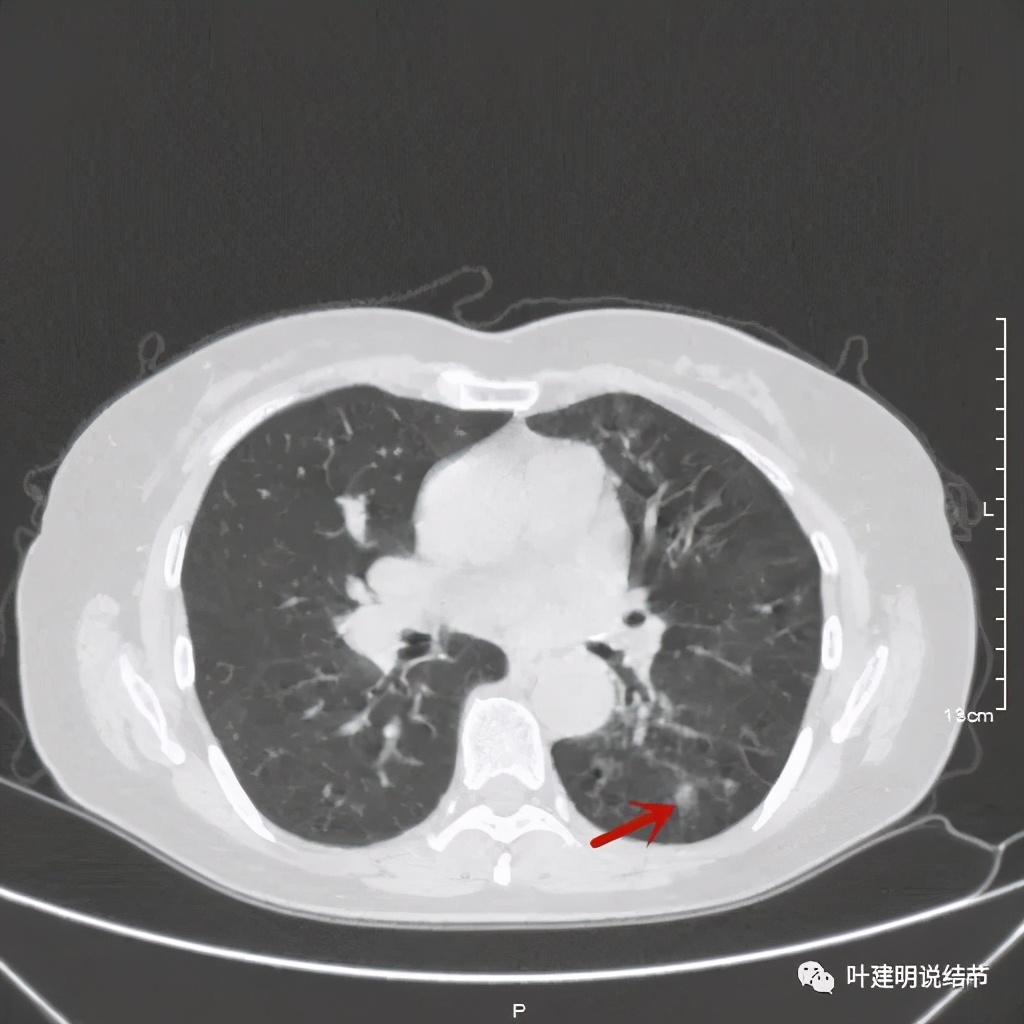

可见同样部位的左下结节已经较去年密度明显低了一些,说明有所吸收了!基本上已经只是磨玻璃密度了。那么其他病灶的情况呢?

也是有所变化,但病灶仍仍在,是异常的。最后这同图上还见到似乎也是实性伴小空腔的病灶(红色三角形标注处),是不是与之前的病灶有点像?